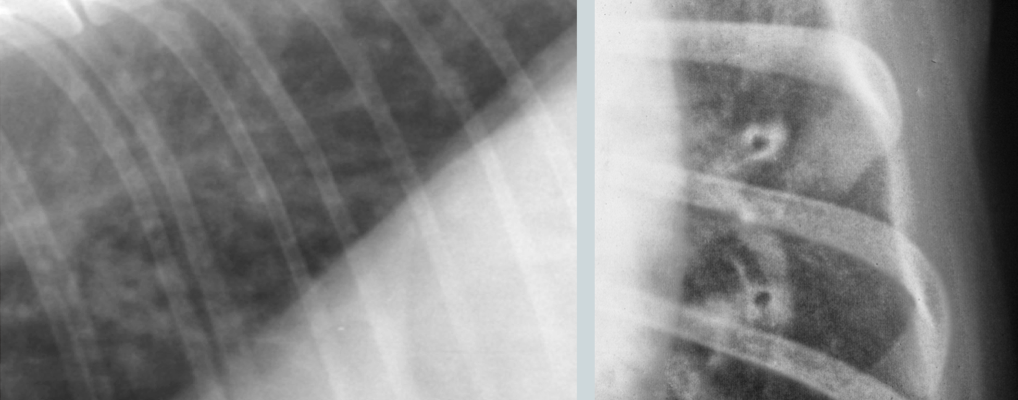

What lung pattern?

Bronchial pattern (see doughnuts)

What lung pattern? What are the arrows pointing to?

Bronchial pattern

tram tracks

Lung pattern?

diffuse severe bronchial pattern